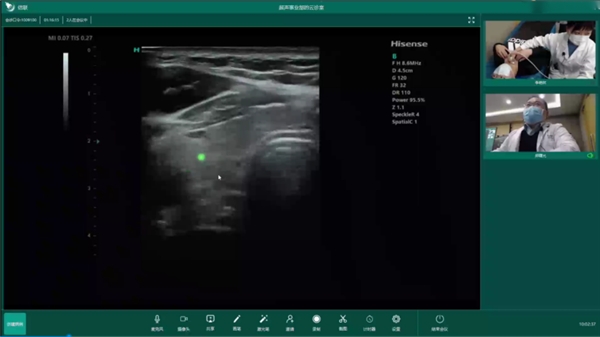

在遠(yuǎn)程超聲方面,海信醫(yī)療自研信聯(lián)遠(yuǎn)程超聲診斷系統(tǒng),采用現(xiàn)代通訊、電子和多媒體計(jì)算機(jī)技術(shù),實(shí)現(xiàn)了超聲遠(yuǎn)程實(shí)時(shí)診斷、遠(yuǎn)程教學(xué)、在線質(zhì)控和交流。前不久,在青島,超聲專家與遠(yuǎn)在1600多公里之外的定西市通渭縣平襄社區(qū)衛(wèi)生服務(wù)中心進(jìn)行了遠(yuǎn)程超聲會診,基層超聲醫(yī)生使用海信超聲為患者進(jìn)行超聲檢查,遠(yuǎn)端專家在線實(shí)時(shí)進(jìn)行操作指導(dǎo)和病例會診,會診大屏同步顯示清晰動態(tài)的超聲圖像。會診過程中,聲音和畫面均做到了同步無延時(shí),遠(yuǎn)程超聲讓基層醫(yī)生和遠(yuǎn)端專家感受到身臨其境的會診體驗(yàn)。

海信遠(yuǎn)程超聲將上級優(yōu)質(zhì)專家資源下沉到基層衛(wèi)生院,專家通過遠(yuǎn)程會診的方式實(shí)時(shí)指導(dǎo)基層超聲醫(yī)師,實(shí)現(xiàn)基層疑難疾病的及時(shí)診療,提升基層醫(yī)生的檢查和診斷能力。憑借超聲產(chǎn)品和平臺優(yōu)勢,海信遠(yuǎn)程超聲已經(jīng)在青島市以及山東省、珠海市、定西市等全國各級醫(yī)院以及體檢中心有了較為廣泛的應(yīng)用,實(shí)現(xiàn)患者就近就醫(yī)。同時(shí),海信醫(yī)療還牽頭編制了首個(gè)遠(yuǎn)程超聲團(tuán)體標(biāo)準(zhǔn),填補(bǔ)了該領(lǐng)域的行業(yè)空白,對于遠(yuǎn)程超聲診斷工作的開展具有積極的指導(dǎo)意義。